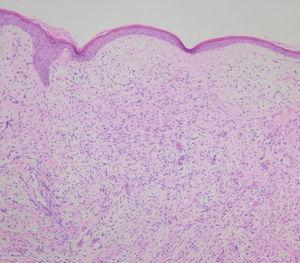

Aportaban una RM realizada en febrero de 2003 en la que ya se apreciaba una tumoración de varios centímetros en cuero cabelludo que afectaba a la piel y el tejido celular subcutáneo. Una vez estabilizada hemodinámicamente, se realizó una biopsia incisional de la tumoración (figs. 2 y 3).

Fig. 2.--Neoplasia que infiltra de forma difusa la dermis y el tejido celular subcutáneo.

En el examen histológico se observó una neoformación celular de crecimiento difuso que abarcaba profundamente toda la dermis y el tejido celular subcutáneo, con efecto compresivo sobre la epidermis, que se encontraba adelgazada. Las células tumorales eran de aspecto pleomórfico, abigarrado, se acompañaban de algunas células gigantes multinucleadas y estaban dispuestas de forma desordenada. También infiltraban paredes vasculares y tractos nerviosos. Las células neoplásicas fueron S100 y vimentina positivas. El antígeno Ki-67 fue expresado en el 40 % de las células del tumor. El resto de técnicas inmunohistoquímicas realizadas fueron negativas, incluyendo HMB-45, citoqueratinas, actina, desmina, factor VIII, antígeno leucocitario común y enolasa neuronal específica.